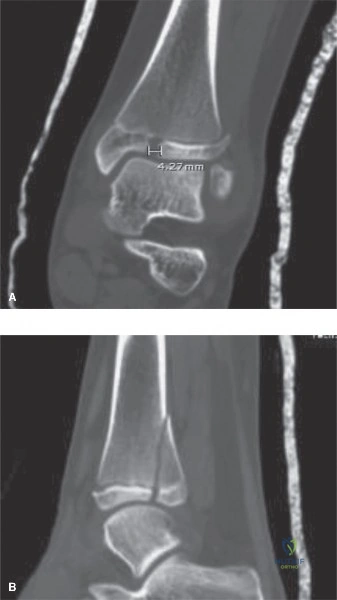

Upon arrival at our trauma center, portable radiographs were obtained with the patient remaining in the traction splint (Figure 10-11). These in-traction films are exceptionally valuable for several reasons. First, they allow the surgeon to assess the "personality" of the fracture once the gross overriding has been reduced. In this case, the traction films confirmed that the fracture was length-stable; meaning, once pulled out to length, the cortical ends could be opposed without a massive comminuted segment that would lead to telescoping. Second, these films help rule out any subtle, non-displaced extensions of the fracture line into the proximal or distal metaphysis that might have been obscured by the initial deformity. The alignment in traction showed excellent restoration of length and a significant improvement in the angular deformity.

Pre-operative templating is a critical phase of the diagnostic workup, particularly when planning for flexible intramedullary nailing. The surgeon must carefully measure the narrowest diameter of the femoral medullary canal, known as the isthmus, on both the AP and lateral radiographic views. The fundamental biomechanical principle of titanium elastic nails (TENs) dictates that the combined diameter of the two chosen nails should fill approximately 80% of the narrowest portion of the canal. Therefore, the formula used is: (Canal Diameter at Isthmus × 0.4) = Individual Nail Diameter. For example, if the isthmus measures 9 millimeters, the ideal nail size would be 3.5 mm or 4.0 mm. Templating also involves assessing the canal diameter at the planned entry points in the distal metaphysis to ensure that the bone can accommodate the insertion of the nails without iatrogenic fracturing.